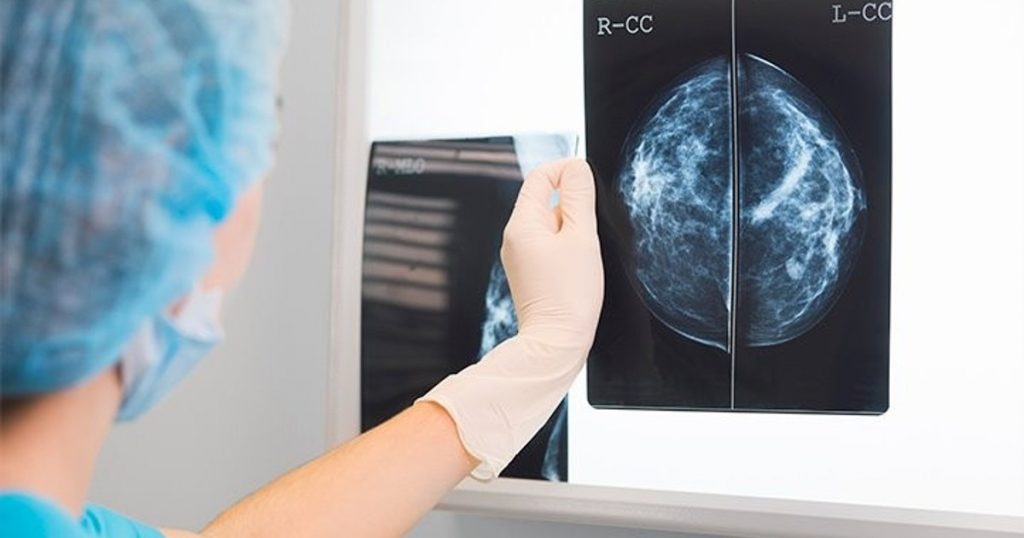

Фото 28 — Маммография для диагностики опухолей